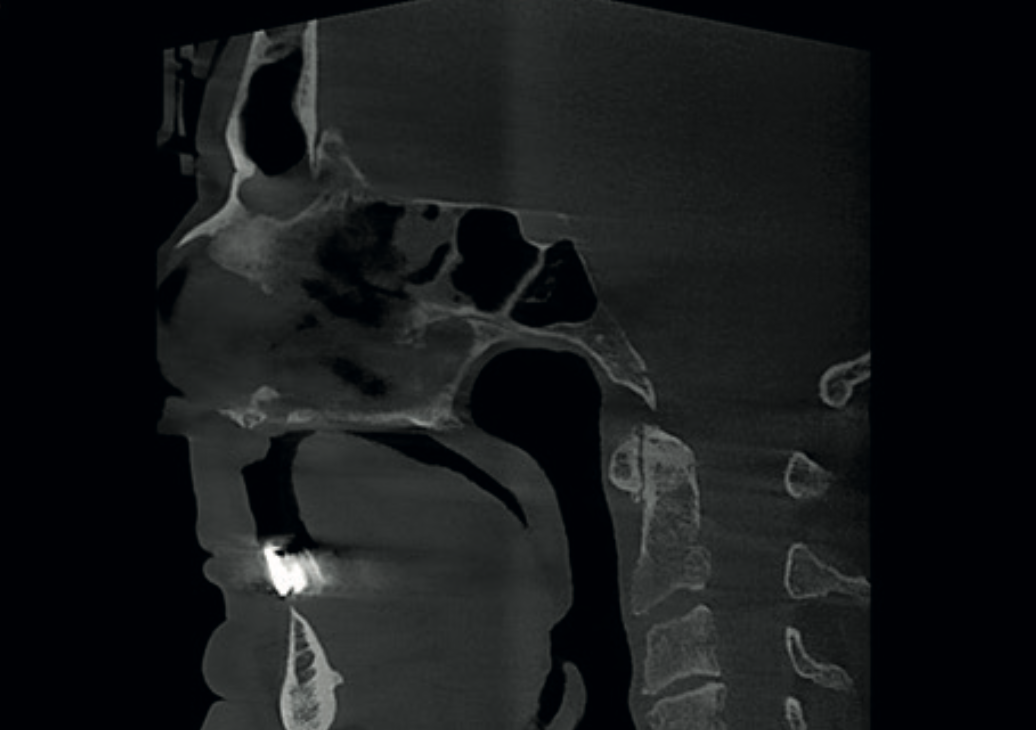

Sagittal CBCT view showing cervical spine osteoarthrosis at C1-C2 and C3-C4

Finding 3

Cervical spine osteoarthrosis

Narrowing of the C1–C2 joint space with subchondral sclerosis and small osteophytes. Reduced C3–C4 joint height also noted.